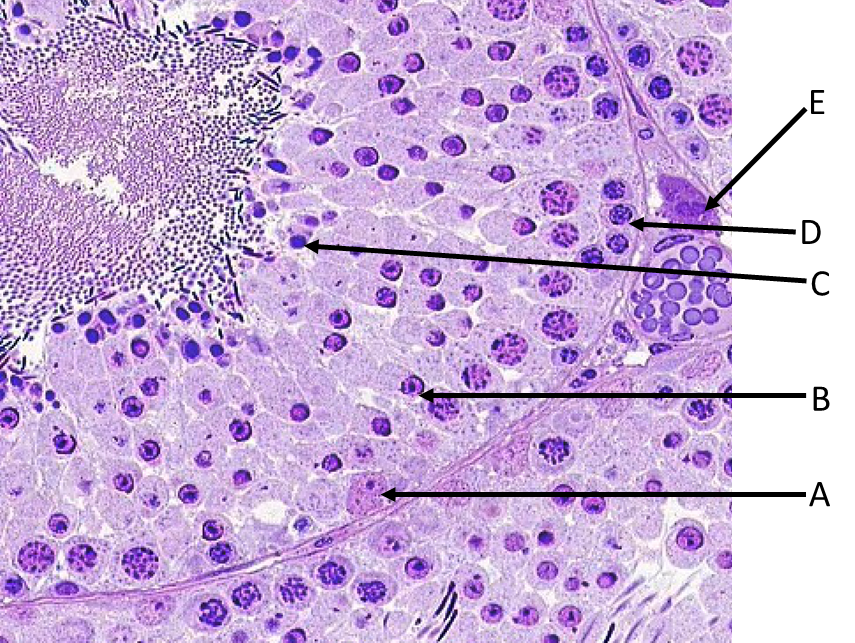

Which cell type shown would have the most abundant receptors for luteinizing hormone (LH)?

A. A

B. B

C. C

D. D

E. E

B.

Which of the labeled cells is a stem cell for sperm production?

A. A

B. B

C. C

D. D

E. E

D. D

Which of the labeled cells secretes androgen binding protein involved in sperm maturation?

A. A

B. B

C. C

D. D

E. E

A.A